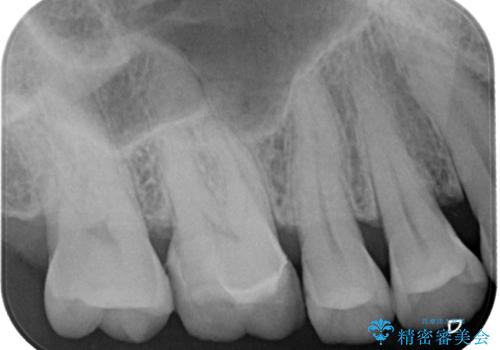

特に異常もなく見た目、噛み合わせともに満足していただけました。

ラバーダム防湿を行い、セラミックの接着をすることで、唾液や血液などの接着阻害因子を排除することができます。

今後はメンテナンスで通ってもらいながら経過を診ていく予定です。